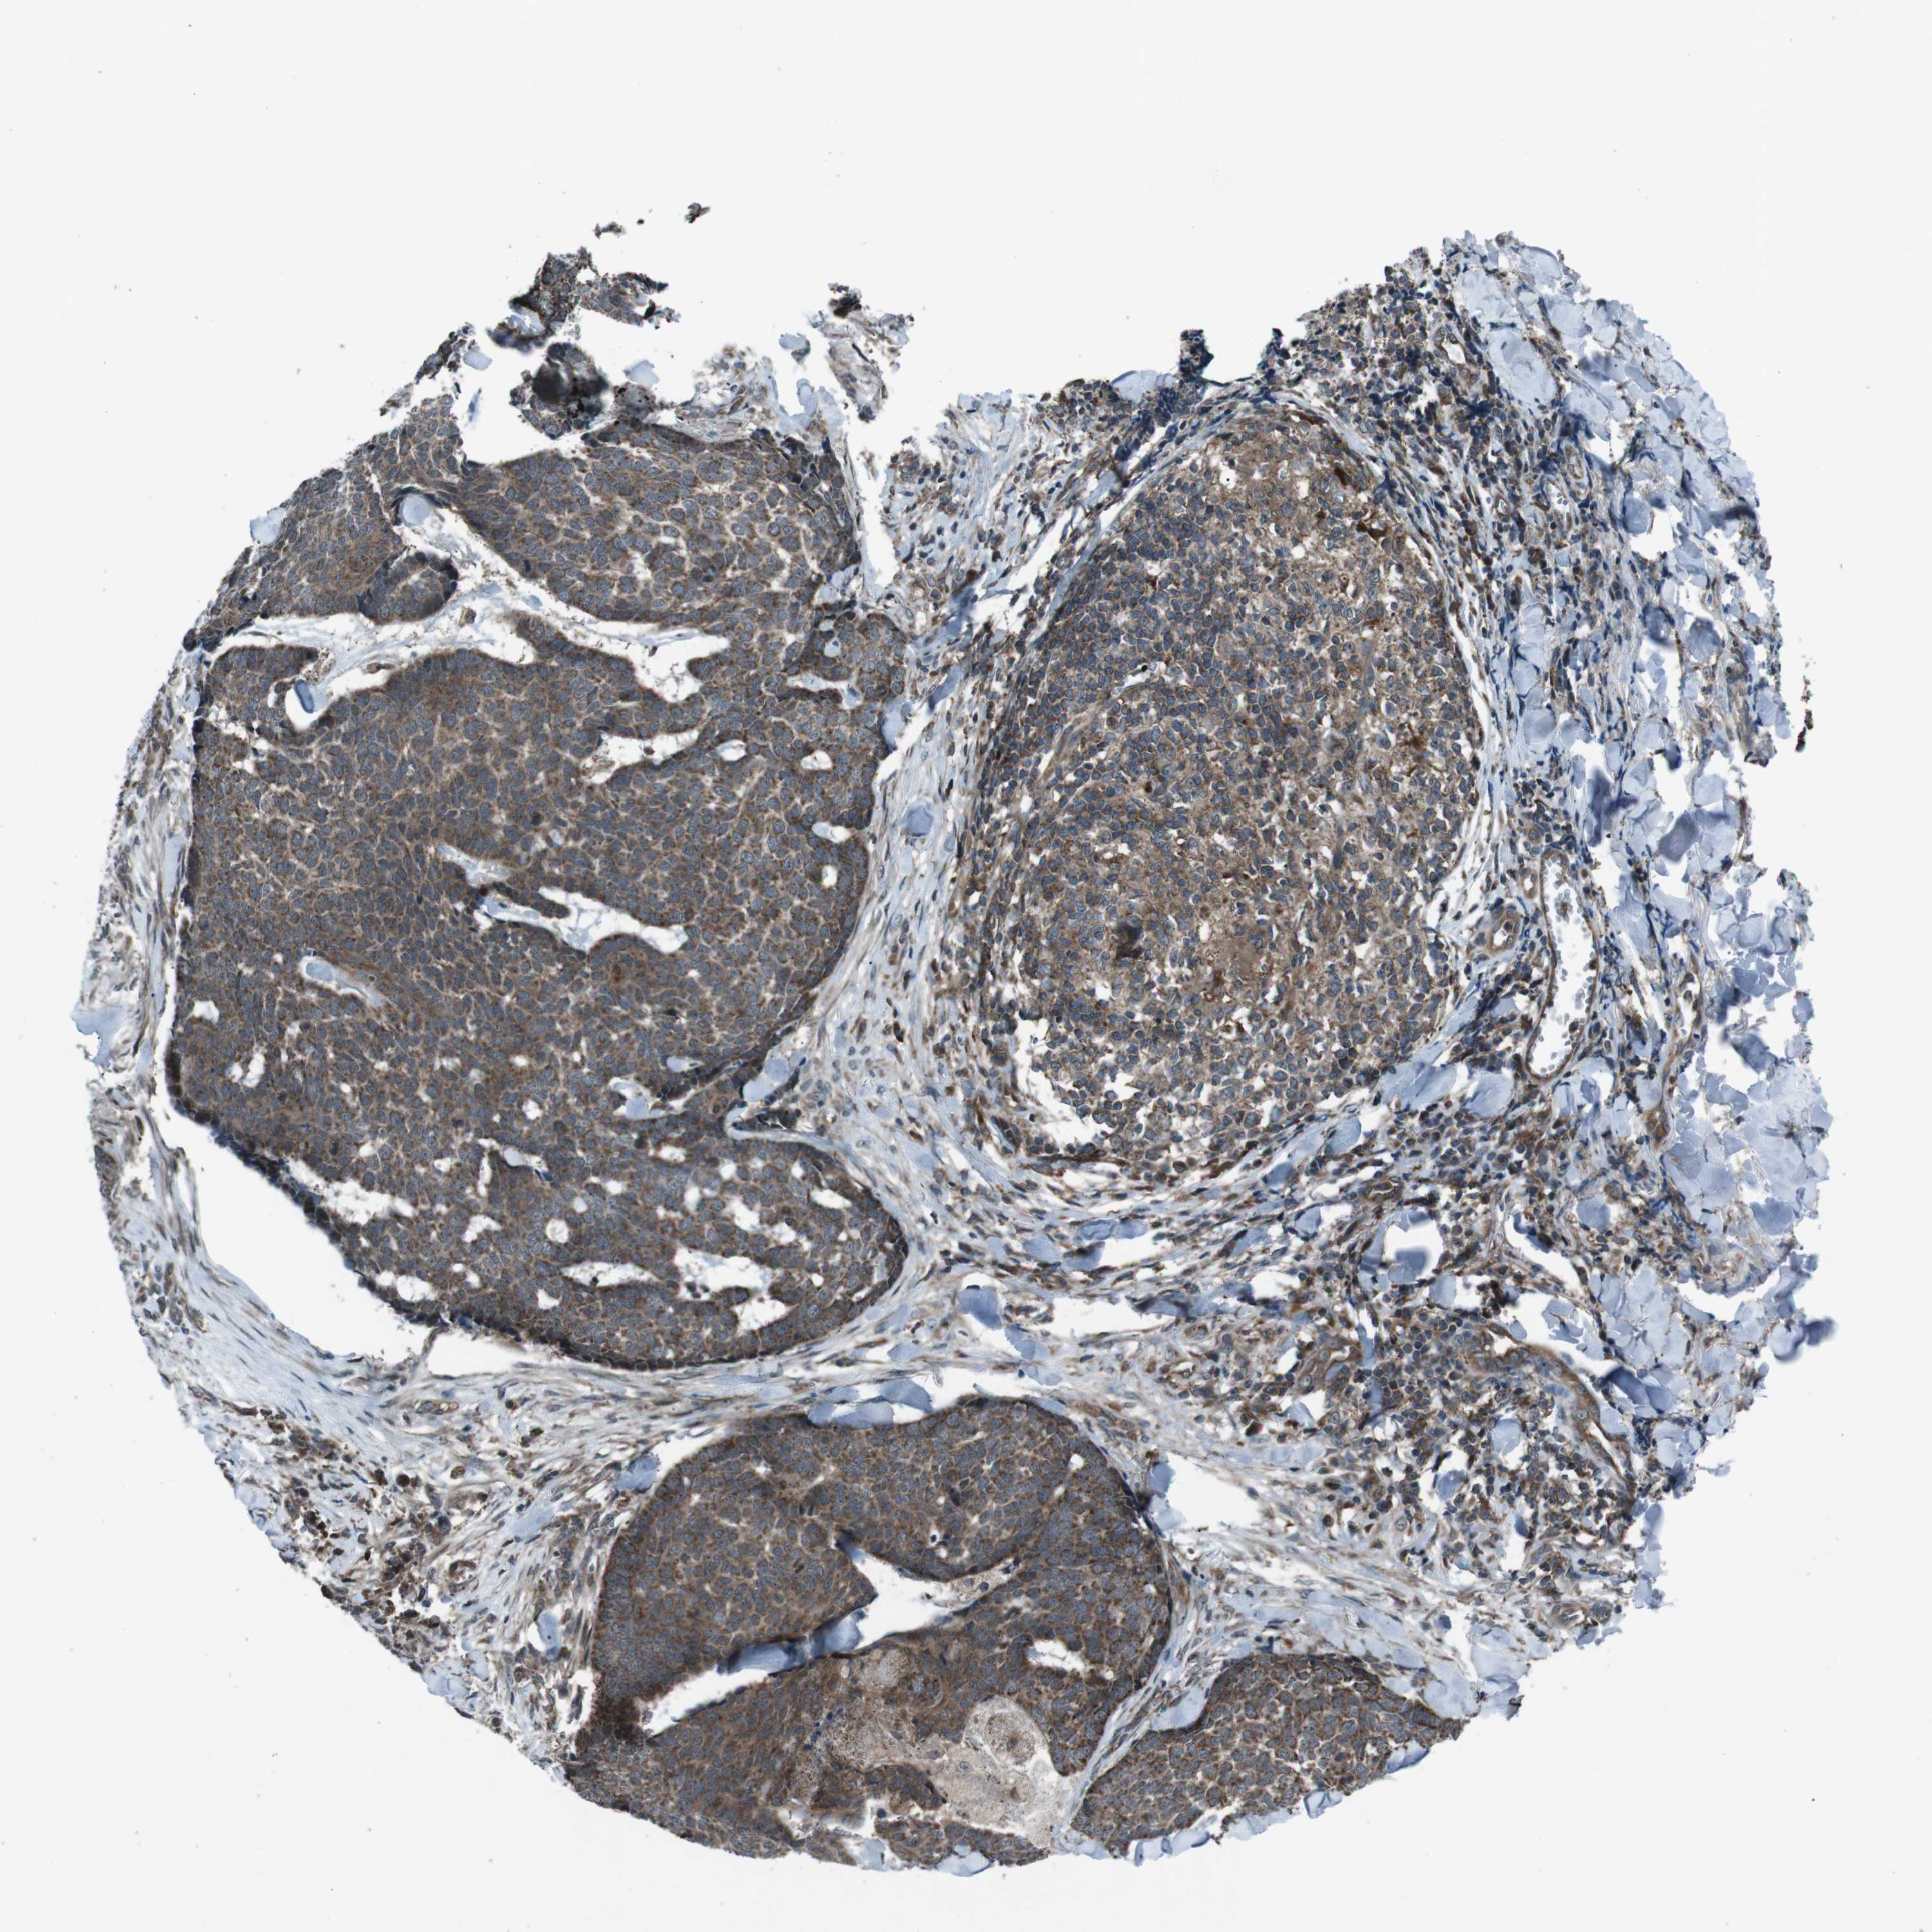

SKIN CANCER - Protein expressioni

A mouse-over function shows sample information and annotation data. Click on an image to view it in a full screen mode. Samples can be filtered based on level of antibody staining by selecting one or several of the following categories: high, medium, low and not detected. The assay and annotation is described here.

Antibody stainingi

Antibody staining in the annotated cell types in the current human tissue is reported as not detected, low, medium, or high, based on conventional immunohistochemistry profiling in selected tissues. This score is based on the combination of the staining intensity and fraction of stained cells.

Each image is clickable and will lead to virtual microscopy that enables deeper exploration of all samples and also displays staining intensity scores, fraction scores and subcellular localization as well as patient and tissue information for each sample.

Antibody HPA007293

Squamous cell carcinoma, NOS